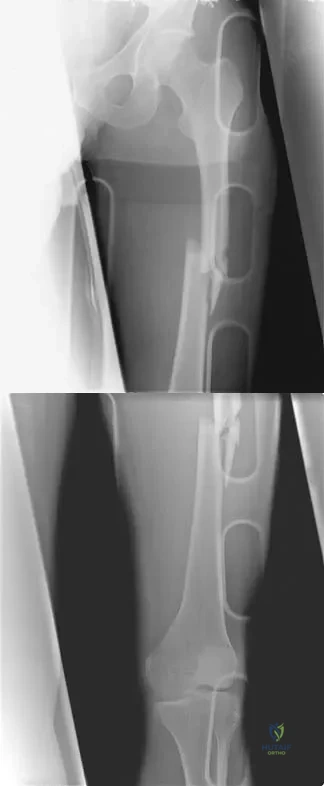

A teenager is undergoing a correction of deformity and lengthening of the femur. Distractions are proceeding as expected; however, during his 6-week follow-up examination, the patient reports that the distraction motors have become harder to turn over for the past 2 to 3 days. Figures 37a and 37b show current radiographs. What is the most likely complication being encountered?